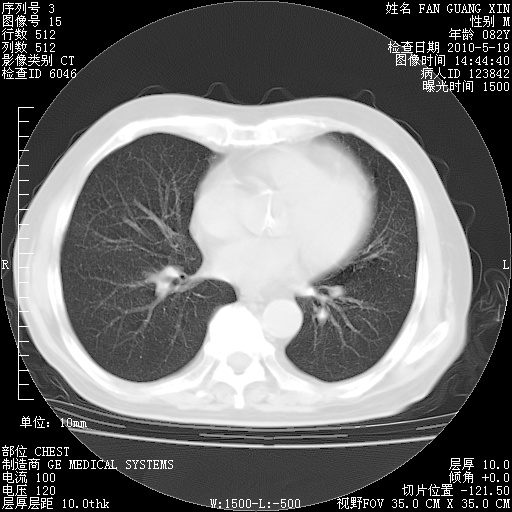

可改为口服强的松40-50mg/d治疗,若病情仍稳定,胸部阴影不再吸收可逐渐减量